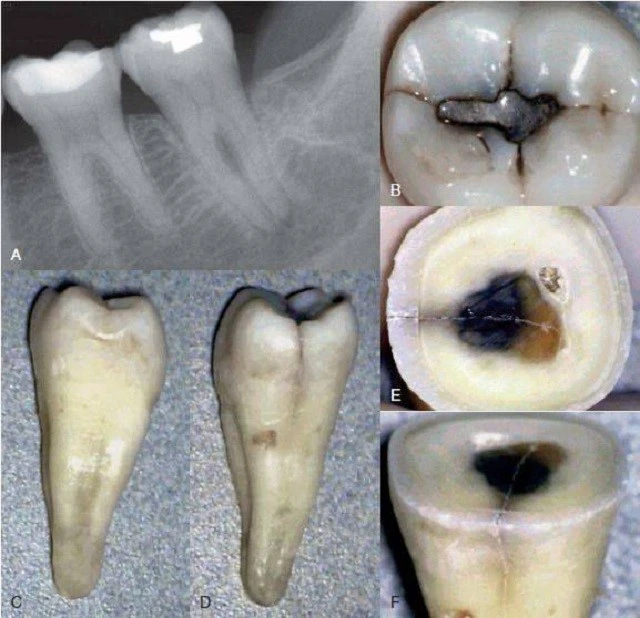

Đôi lúc nứt dọc chân răng hoặc chia chân răng có thể chẩn đoán rõ ràng bằng

X-quang. Tuy nhiên, hầu hết trường hợp đường nứt nằm trên một mặt phẳng và không nhận ra được trên ,X-quang. Trong một nghiên cứu ở những răng đã được nhổ, các nhà nghiên cứu cho rằng sẽ thấy được vết nứt khi tia X được chiếu trong vòng 4 độ đối với mặt phẳng nứt. Nếu nằm ngoài góc này thì không thấy rõ được đường nứt. Họ cũng nhận thấy rằng nếu có nứt dọc thì chúng chỉ thấy được trên

X-quang trong 35.7% trường hợp.

Trường hợp không phát hiện được tình trạng nứt dọc chân răng trên phim X-quang

Đường xi măng

Chia chân răng có thể mở rộng thừ mặt gần đến mặt xa của răng, thường đường nứt này xảy ra sau khi thực hiện điều trị nội nha. Đôi lúc sẽ thấy một hình ảnh “đường xi măng” dọc hoặc băng ngang qua chân răng. Phần xi măng bị đẩy qua đường nứt, sau đó có thể thấy được nó trên X-quang. Nha sĩ có thể nhầm với hình ảnh phần xi măng bị đẩy qua ống tuỷ phụ, nhưng trong trường hợp nứt răng thì phần xi măng sẽ bị đẩy ra khuếch tán hơn và không có hình ảnh ống tuỷ bên đổ ra từ ống tuỷ chính.

Hình ảnh mất xương như “vòng sáng”

Thông thường khi một răng chết tuỷ thì hình ảnh ,X-quang của nó sẽ thay đổi, mất xương xảy ra ở vùng chóp. Tuy nhiên, khi một răng bị nứt dọc hoặc chia chân răng, vùng mất xương có khuynh hướng cho hình ảnh “vòng sáng”, thấu quang xung quanh chân răng. Vùng thấu quang cũng có thể đi dọc toàn bộ một bên chân răng và thường được gọi là tổn thương “dạng chữ J”.

Vùng mất xương khu trú

Bác sĩ cần chú ý đến những thay đổi bất thường trên X-quang như mất xương rộng nhưng chỉ khu trú ở một răng và không có bệnh lý nha chu tiến triển. Điều này có thể gợi ý nứt dọc chân răng hoặc chia chân răng. Khi nghi ngờ có nứt dọc chân răng, bác sĩ cần chú ý tìm những dấu hiệu sau:

– Ống tuỷ rộng hơn bình thường so với ống tuỷ của chân răng cạnh đó

– Vùng thấu quang xuất hiện giữa trục chính của vật liệu trám bít ống tuỷ (hoặc chốt) và thành ống tuỷ.

– Vùng mất xương ở phía gần và xa chân răng. Khi nứt dọc chân răng hoặc chia chân răng mở rộng từ phía gần đến phía xa của răng thì thường toàn bộ dây chằng nha chu quanh răng sẽ giãn rộng không điển hình.

E. ĐÁNH GIÁ TÌNH TRẠNG NHA CHU

Thông thường, chia chân răng liên quan đến việc tiêu xương tiếp giáp với vùng gãy. Nếu không được phát hiện sẽ tạo nên một vùng khiếm khuyết trong xương dạng chữ V mở rộng về phía chóp. Túi nha chu liên quan đến quá trình mất xương này thường có giới hạn hẹp và sâu; thường sẽ có thêm một khiếm khuyết tương tự như vậy ở phía mặt răng đối diện 180 độ (chẳng hạn như mặt phía bên kia của đường nứt). Khi đặt cây thăm dò nha chu vào túi, nó sẽ nằm chặt trong túi, giới hạn việc di chuyển cây từ bên này qua bên kia. Tổn tương nha chu này là điểm đặc trưng trên lâm sàng.